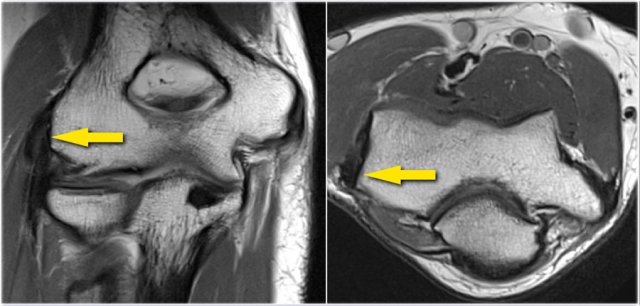

On the coronal images there is a beautiful anterior bundle of the UCL, but notice that there is osteophyte formation on the medial part of the joint (red arrow).

As we go further posteriorly there is a small area of low signal intensity (yellow arrow), which is an avulsion of part of the UCL.

Continue with the axial scan.

As we look on the axial scan, we can appreciate the huge osteophyte formation.

Notice that the ulnar nerve (blue arrow) is next to these osteophytes and these patients may present with ulnar neuropathy.